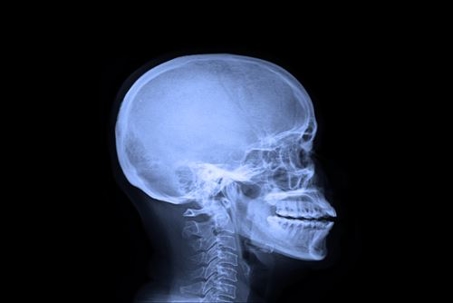

After a car accident, it is not unusual for you to be completely disoriented and dazed as you process what has just happened. This chaotic aftermath can prove quite detrimental as it distracts you from the issue at hand, which is listening to what your body is telling you. Some injuries do not present themselves until long after the accident because our bodies numb us from their full impact as an instinctually protective measure. Therefore, you must constantly be aware of any persistent symptoms which present themselves after an accident. While headaches may seem harmless, they can prove to be quite telling by often indicating a much worse threat.

Many people ignore headaches after an accident because they weren’t directly and physically hit by an impact, but this is one of the worst mistakes you can make. A headache is often a sign that something else is wrong, including underlying injuries like whiplash, concussions, traumatic brain injuries, etc. If your headache is not treated by an expert medical professional, you run the risk of putting your life in grave danger. You should seek medical attention after an accident in any case, but the reasons to do so are far greater if you experience even the slightest symptoms. Not only will this put you and your family’s mind at ease, but it will maximize your chances at a future claim for compensation.